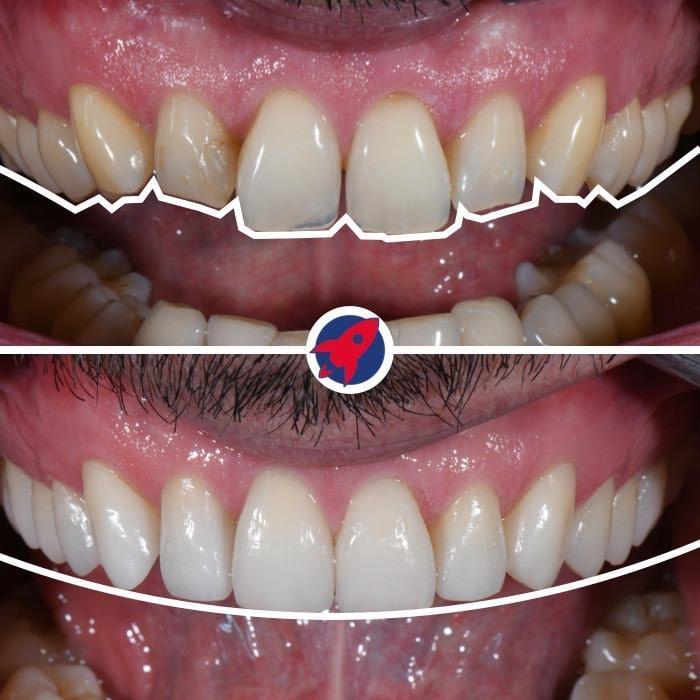

The solution: Dr. Horvath was able to come up with a long-term plan to solve the problem once and for all, and with the help of his lovely wife, we were able to create the necessary space for a crown, remove the implant, and place a brand new, custom-made bridge that was 3D printed literally in three hours. Part of it while I was pregnant.

This is a family practice that really cares about its patients. I have often come to my appointments alone with my baby and have always been warmly welcomed. Everything is planned so that it can be done in as few appointments as possible. As an expat in Switzerland, the reason I originally had treatment done in my home country was the cost of dentistry here. My treatment with Dr. Horvath (including an orthodontic treatment with his wife to align the teeth before the final bridge placement) was mostly covered by my supplementary health insurance in Switzerland, and in the end the whole treatment (including the aesthetic orthodontic treatment!) was cheaper than if I had traveled to my home country to have it done. I was missing a tooth for almost 5 years, and Dr. Horvath gave me brand new teeth in just a few hours 🙂